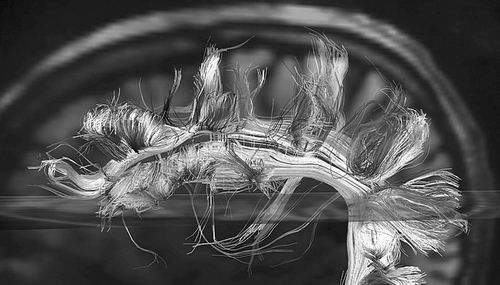

扩散磁共振成像仅是研究人员用来聚焦脑部许多数据的方法之一。

图片来源:Van Wedeen